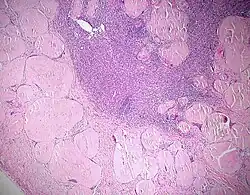

- Käsige Nekrose - Bsp.: Tbc (Epitheloidzelliges Granulom mit Langhans-Riesenzellen und zentraler käsiger Nekrose)

Nekrose

Nekrose ist das intravitale Absterben von Zellen

Mikro: (nach Ablauf der Manifestationszeit!)